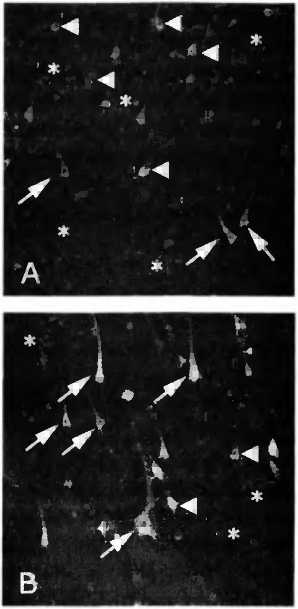

Мы сейчас заняты поисками веществ, которые могли бы вызвать процесс активации нейронов и в других областях мозга. Доктор Роналд Фервер разработал для этого методику, позволяющую на протяжении многих недель выращивать нейроны в тонких срезах мозговой ткани, предоставленной для исследования в период, не превышающий десяти часов после наступления смерти донора. Метод позволяет изучать воздействие потенциально стимулирующих веществ без ущерба для пациента. При этом стволовые клетки, вероятно, выделяют вещество, которое повышает у выращиваемых нейронов способность к выживанию (рис. 33), но что это за вещество, мы так и не знаем.

Рис. 33. Тонкие срезы ткани головною мозга скончавшегося пациента, полученные в течение десятичасового периода с момента смерти. В этом случае клетки мозга могут выращиваться в течение многих недель. Стволовые клетки, по-видимому, выделяют какое-то еще не известное вещество, которое повышает жизнеспособность нейронов в этой культуре. При стандартных условиях роста (А) через 48 дней было обнаружено всего несколько здоровых и активных клеток (стрелки) и гораздо больше клеток с неплотными мембранами (стреловидные треугольники). Их можно узнать по окрашенным ядрам. Кроме того, здесь много ядер мертвых клеток (маленькие шарики, обозначенные звездочками). На срезе (В) видно, что при культивировании такого же препарата мозговой ткани, но со стволовыми клетками того же пациента здесь гораздо больше здоровых активных мозговых клеток (стрелки) и меньше неплотных (стреловидные треугольники) и мертвых клеток.